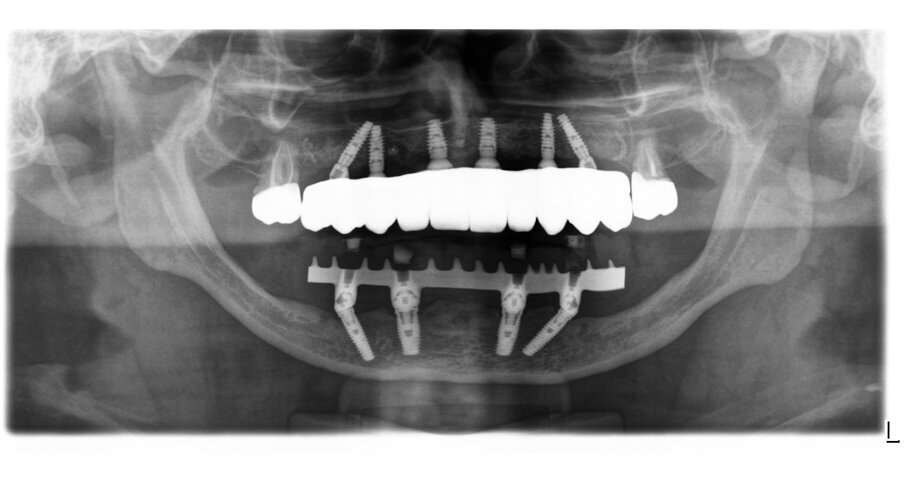

Durante la fase di chirurgia implantare, è stata inizialmente fissata la dima chirurgica sfruttando l’appoggio dento-mucoso; successivamente, è stata eseguita un’incisione lineare crestale e si è proceduto al sollevamento di un lembo vestibolare a tutto spessore e alla rimozione delle mini-viti e della griglia, che essendo osteointegrata in diversi punti è stata rimossa in diversi frammenti. La percentuale di rigenerazione, ovvero il rapporto tra il volume osseo rigenerato e il volume osseo pianificato, è stato calcolato essere del 96% (Figg. 25-29). La dima chirurgica è stata riposizionata e fissata nuovamente mediante i pin di fissaggio precedente preparati, non avendo più il supporto mucoso. Usando una tecnica di sotto-preparazione, sono stati realizzati i siti implantari e sono poi stati inseriti i 6 impianti programmati: 4 impianti dritti con dimensione 10 x 3.7 mm e 2 impianti angolati a 25° con dimensione 12 x 3.7 mm, al fine di evitare il seno mascellare (BTK implant Isy+, Biotec Srl, Dueville, Vicenza, Italy) (Fig. 30).

Dopo 4 mesi, è stata eseguita la riapertura degli impianti, verificando la loro osteointegrazione e applicando su di essi i rispettivi multi-unit abutment (MUA); inoltre, è stata eseguita una gestione del tessuto cheratinizzato mediante un lembo palatino a riposizionamento vestibolare (Fig. 31). Nei mesi successivi, sono state eseguite tutte le fasi protesiche che hanno portato alla realizzazione di una protesi fissa definitiva in zirconia e ceramica, avvitata sui 6 impianti, tipo “Toronto bridge” (Fig. 32). Il paziente è stato istruito alla corretta igiene domiciliare ed è stato inserito in un programma di mantenimento con sedute di igiene professionale ogni 6 mesi; e controlli radiografici mediante rx endorali e controlli clinici con smontaggio/rimontaggio della protesi fissa ogni 12 mesi (Fig. 33).